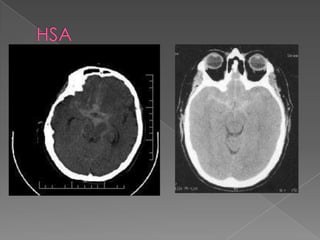

 Primer estudioen el abordaje  Cortes de 3 mm. desde la base del cráneo.  Paralela al paladar duro.  Hemoglobina < 10 gr/dl aparece isodensa.  Artificios por movilización del paciente. Am J Emer Med 2006;24:859-863

 Predecir lalocalización 70%  Hemorragia intraventricular (PICA)  Hemorragia en la cisura interhemisférica (Acom)  Hemorragia en el valle silviano (ACM / com post)

Grado 1: TC normal. Neurosurgery 1980;6:1-9

Grado 2: difusa o capa vertical < 1 mm Neurosurgery 1980;6:1-9

Grado 3: Coagulos localizados y capas > 1 mm. Neurosurgery 1980;6:1-9

Grado 4: Coágulo intracerebral o intraventricular. Neurosurgery 1980;6:1-9